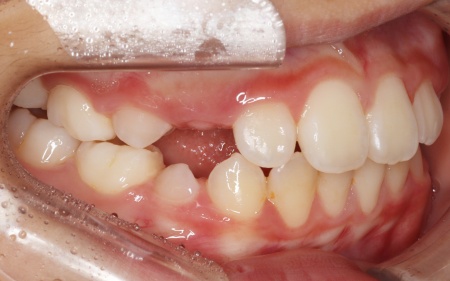

後日、噛み合わせや歯並びが整ったことを確認し、矯正治療を終了しました。

現在は、3ヶ月に1回のペースで来院いただきながら経過観察を続け、永久歯の生え変わりに合わせて、必要に応じてリテーナー(保定装置)の調整も行っています。